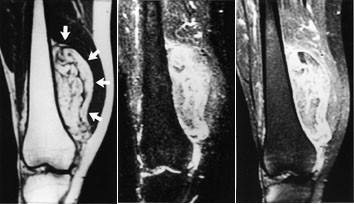

Ved osteogent sarkom og Ewings sarkom kan MR med snittplan i knokkelens lengdeakse nøyaktig fastslå øvre og nedre grense for tumorutbredelse i beinmargen (fig 5), påvise metastaser innenfor samme margrom og innvekst i ledd. Dette er forhold som har stor betydning for omfanget av kirurgiske inngrep. Som regel har tumor på diagnosetidspunktet brutt gjennom knokkelen og gitt opphav til en ekstraossøs komponent. Med snittplan perpendikulært på knokkelen kan MR vise om tumor affiserer kar og nerver, og hvilke muskler den ligger an mot eller infiltrerer. MR kan styre biopsitakingen til de områder av tumor hvor det er størst sannsynlighet for å finne representativt vev.